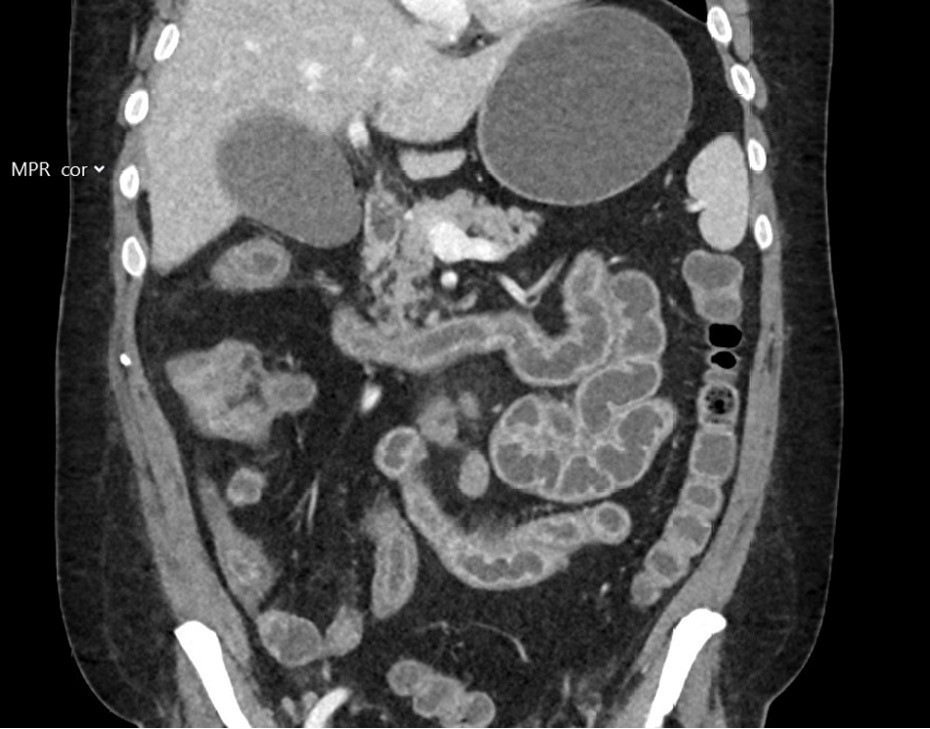

Pasienten ble innlagt tre døgn senere med redusert allmenntilstand, magesmerter og vanntynne tømminger. Ved innleggelsen var han afebril med normale vitale parametre. Blodprøver viste CRP på 12 mg/L med normale nivåer av leukocytter, kreatinin på 59 μmol/L (60–105), estimert glomerulær filtrasjonsrate (eGFR) på 108 mL/min og normale elektrolytter. Blodkulturer og avføringsprøver ble sikret, sistnevnte var negative for Clostridioides difficile og tarmpatogenpanel. Dyrkningsprøver for Aeromonas, Vibrio og Plesiomonas i avføring var negative. Pasienten utviklet økende smerter i nedre del av buken, og det ble rekvirert CT-undersøkelse av abdomen og bekken to dager etter innleggelse som viste uttalt enterokolitt med inflammasjon i hele tynntarmen og høyre del av tykktarmen (figur 2). Dagen etter ble det anlagt fekalkatetersystem i rektum for avlasting av uttalt sår hud rundt endetarmsåpningen, og pasienten fikk parenteral ernæring og elektrolyttsubstitusjon. Fire dager etter innleggelse viste PCR-undersøkelse for cytomegalovirus (CMV) i EDTA-plasma < 110 IE/mL (svak positiv).